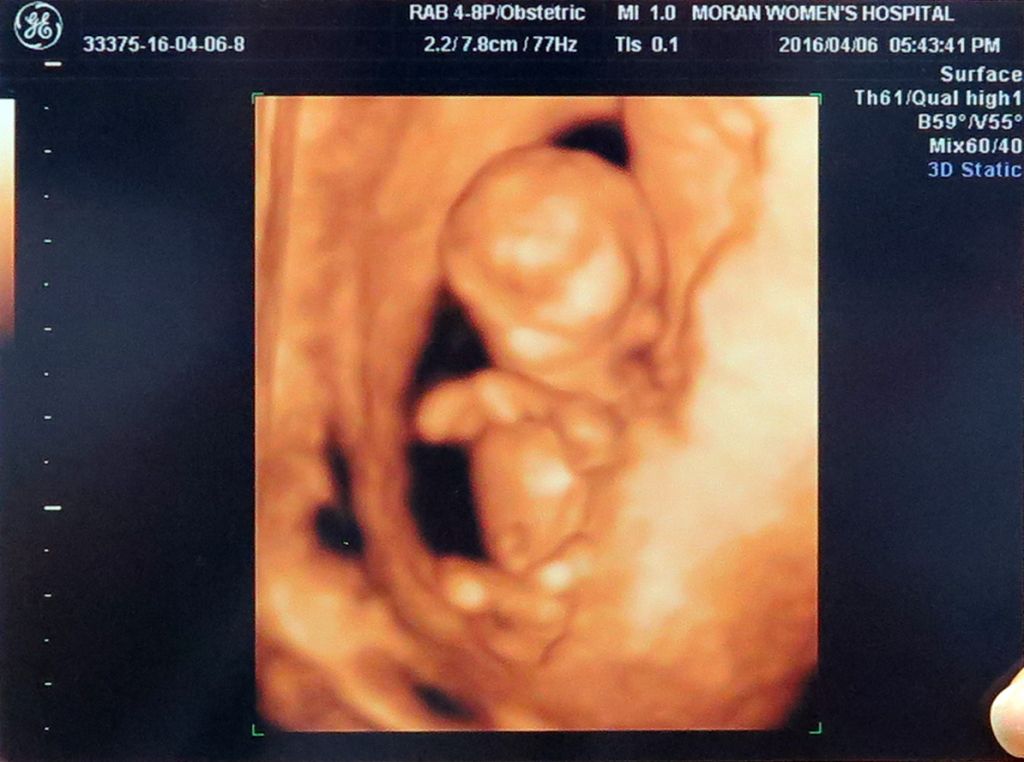

정말 신묘막측이 실감나네요.

우리 별이,,,,

건강하게 자라줘서 고맙고.

한울아! 정말 수고많다.

어제,오늘 너무 바쁜 탓에 피곤하지만 퇴근 후 우리

별이 소식에 하루의 피곤이 싹 가시는구나.

너무너무신기하고 감동이다 ㅎㅎ

노래도 너무 잘 어울리네

별이가 건강하다니 감사하고..

별이엄마는 어서 입덧이 끝나고 마음껏

먹어야 될거같고..

별이아빠는 별이랑 만나기전에 몸매관리

좀해야 할듯 하네요 ㅋㅋ

암튼 너무 너무 감사하다 \(^o^)/

별이 모습 보니 신기하고 반가워 ㅋㅋ

건강하게 잘 있어줘 고마워~~^^